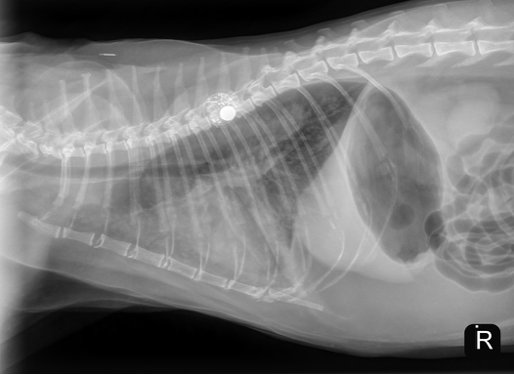

Cardiology Case of the Month: Fluid Intolerant/Overload Congestive Heart Failure in Cats

A 9 yo MN DSH initially presented to PVESC Emergency Department in September 2025 for further evaluation of a decreased appetite. He had historically been…